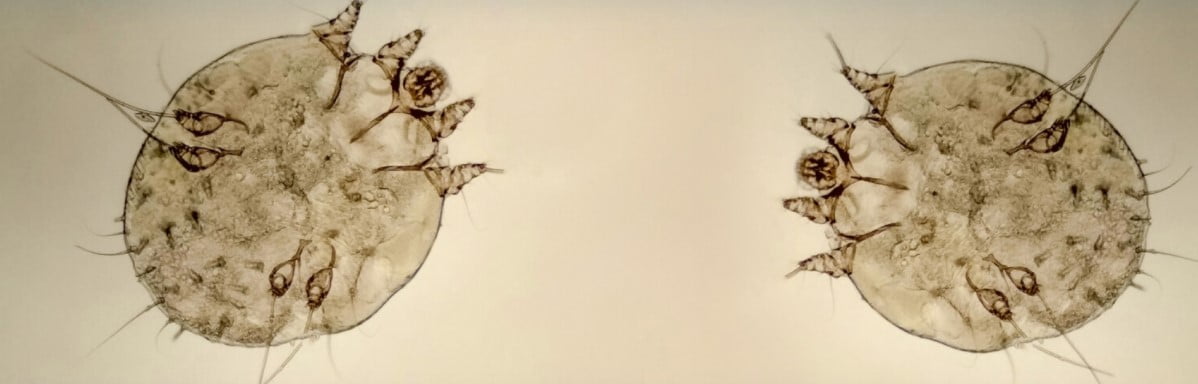

Uyuz hastalığı hakkında bilgilendirmede bulunan Uzm. Dr. Mine Kaya, “Uyuz hastalığı;

Sarcoptes scabiei adı verilen akarların sebep olduğu yaygın görülen bir hastalıktır. Gözle

görülmesi mümkün olmayan bu akarlar, cildin dokusuna yerleşip, kişilerde yoğun kaşıntı